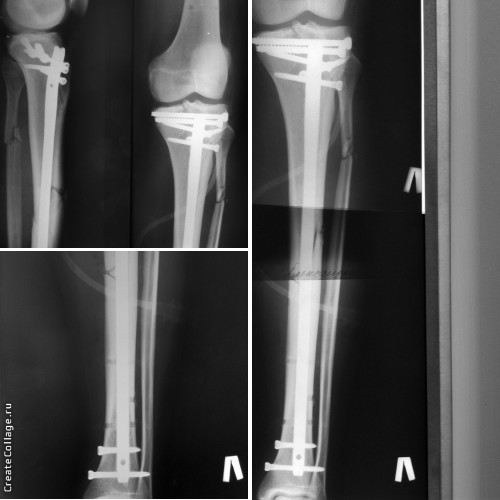

Re: Перелом плато и диафиза большеберцовой кости

Остеосинтез по Илизарову

П/операционные снимки выложил.

Результат

Реимпакция всё же понадобилась, без нее не получалась репозиция плато.

Реимпакция была сделана закрыто под ЭОП. Фрагмент импрессии был хорошо виден. После этого - репозиция, МОС канюлированными винтами, БИОС. Проксимальный блокировка 3 винтами 5,0.